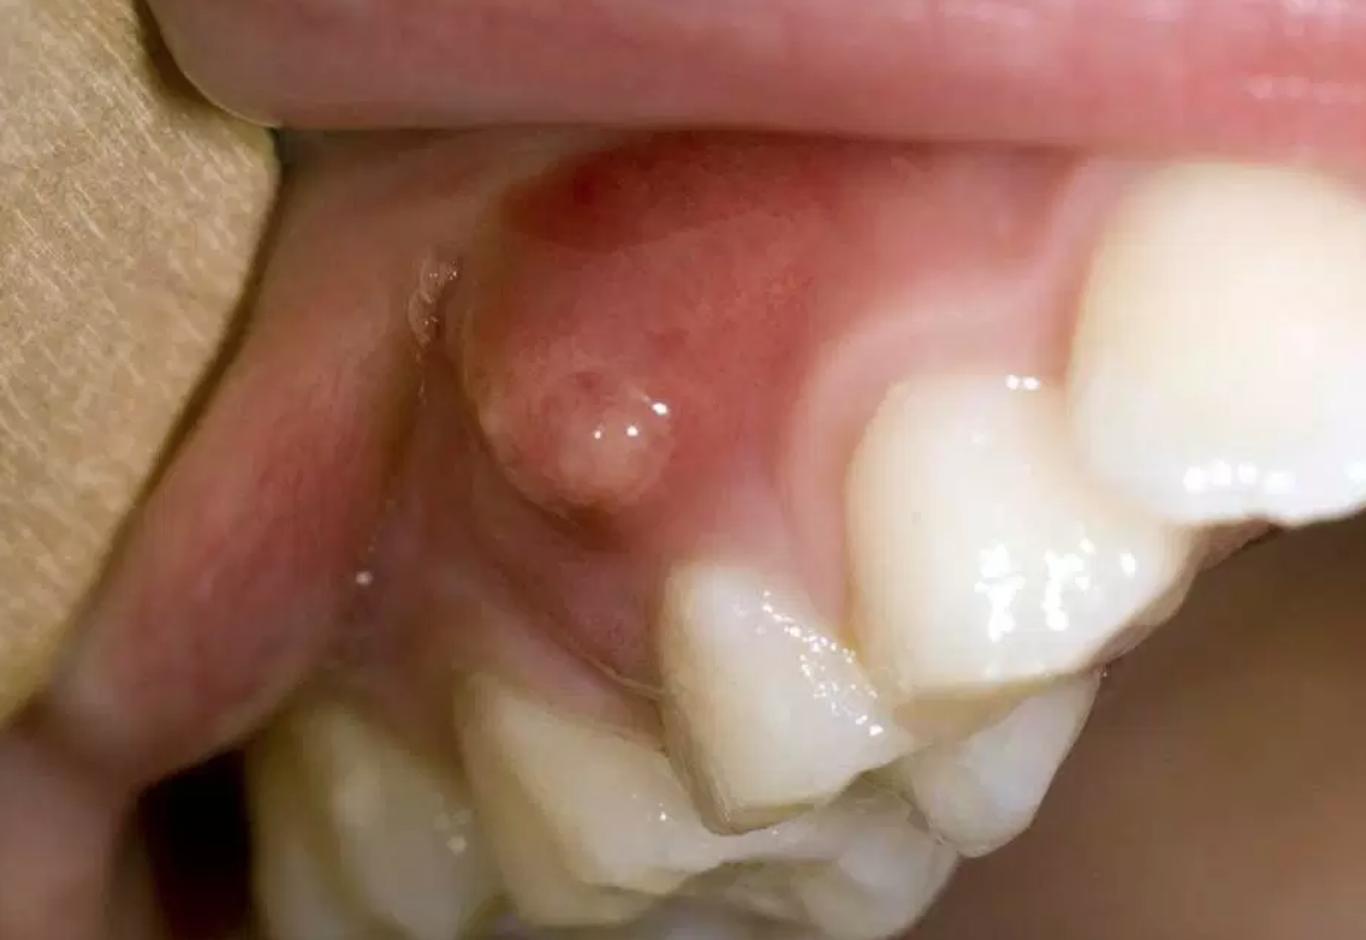

In the management of compromised dentition, the recurrence of pathology presents a pivotal decision point. The presentation of a bump on gum after root canal—indicative of chronic apical abscess—moves the tooth from a "stable" category to a "failing" category. As a senior consultant at Luxe Smile Studio, my role is to evaluate the strategic viability of retaining such a tooth. We must weigh the prognosis of retreatment against the predictability of extraction and implant replacement. This is not merely about treating an infection; it is about forecasting the 5- and 10-year survival capability of the dental unit in the context of the patient's overall health and financial investment.

The sinus tract indicates active bone destruction.

The bump on gum after root canal is essentially a drain for a bony cavity. We must evaluate the size of this lesion via CBCT (3D imaging). If the lesion has eroded the buccal cortical plate significantly, or encroaches on the sinus or nerve canal, the risk of retaining the tooth increases. Prolonged retention of a failing tooth consumes the very bone needed for a future implant. Strategically, it is sometimes wiser to extract a tooth with a bump on gum after root canal sooner rather than later to preserve the alveolar ridge for replacement therapy.

Microsurgery removes the infected root tip (3mm) and seals the end. However, this shortens the root. If the tooth already has short roots or significant periodontal bone loss, removing another 3mm may destabilize the tooth. A bump on gum after root canal on a tooth with a poor crown-to-root ratio is often a terminal sign. The strategic advice here is often extraction, as the surgical solution would only yield a transient extension of life (2-3 years) before mechanical failure occurs.